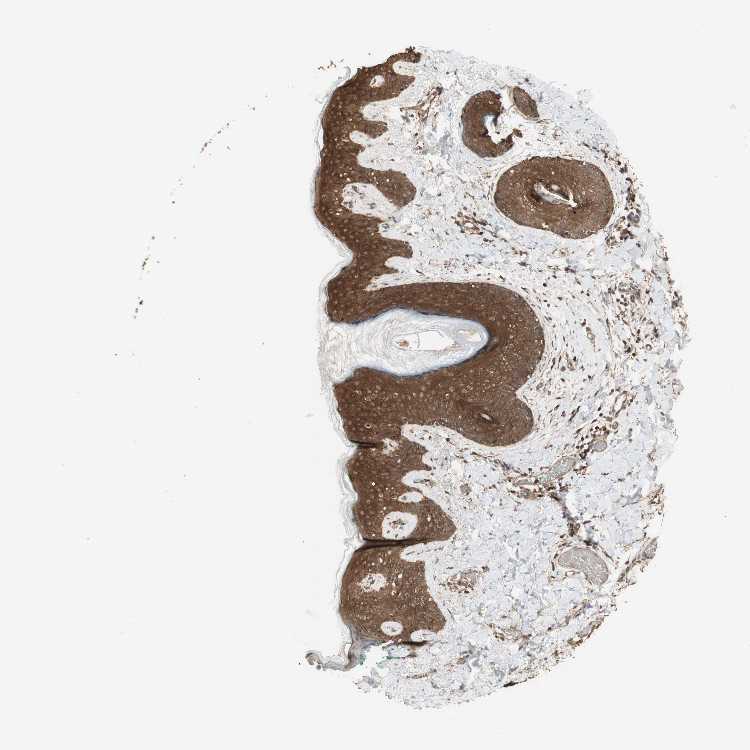

SKIN 1 - Antibody stainingi

Antibody staining in the annotated cell types in the current human tissue is reported as not detected, low, medium, or high, based on conventional immunohistochemistry profiling in selected tissues. This score is based on the combination of the staining intensity and fraction of stained cells.

Each image is clickable and will lead to virtual microscopy that enables deeper exploration of all samples and also displays staining intensity scores, fraction scores and subcellular localization as well as patient and tissue information for each sample.

Antibody HPA007925Antibody HPA011212Antibody CAB003759Antibody CAB080290

Langerhans Medium-MediumHigh

Cells in basal layer -High--

Cells in corneal layer -Not detected--

Cells in granular layer -High--

Cells in spinous layer -High--

Endothelial cells -Medium--

Extracellular matrix -Not detected--

Fibroblasts Medium-Not detectedHigh

Fibrohistiocytic cells -High--

Hair follicles -High--

Keratinocytes Medium-MediumHigh

Langerhans cells -High--

Lymphocytes -High--

Melanocytes MediumHighMediumHigh

Vascular mural cells -Not detected--